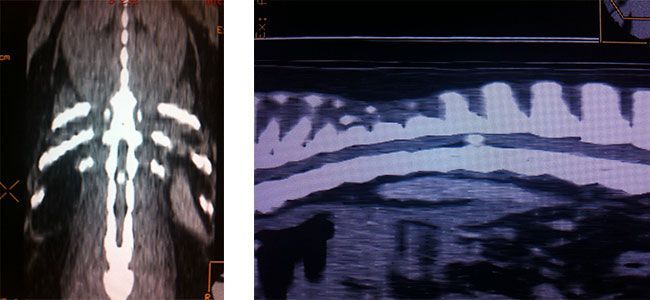

Hernia de disco

Se produce una compresión de la médula espinal en la columna, debido a que un disco intervertebral ocupa un espacio en el canal medular. Pueden producir desde un simple dolor o malestar, a que el animal llegue paralítico.

La mayoría de los casos se resuelven mediante un tratamiento conservador, pero las más graves necesitan de una cirugía, que trata de descomprimir la médula espinal, extrayendo el material de disco que comprime el canal medular.

Para llegar a un correcto diagnóstico, siempre es necesario la realización de un TAC o SCANNER, en el cual vamos a ver la localización exacta de la hernia, para poder planificar la cirugía de forma muy precisa.

El resultado, si el diagnóstico es temprano, suele ser muy satisfactorio y el 90 % de los pacientes operados pueden volver a caminar.